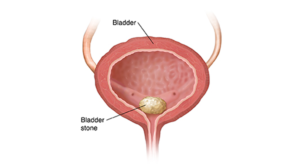

سنگ مثانه ۱۱ میلیمتری چیست و چگونه ایجاد می شود؟

سنگ مثانه زمانی تشکیل می شود که ادرار در مثانه باقی مانده و مواد معدنی موجود در آن (مانند کلسیم یا اسید اوریک) متبلور شوند. این کریستال ها به مرور زمان به هم پیوسته و توده های سختی را ایجاد می کنند. سنگ مثانه ۱۱ میلی متری از نظر ابعاد، سنگی متوسط رو به بزرگ محسوب می شود که به ندرت به صورت خودبه خودی دفع می گردد.

پاسخ این است که به دلیل قطر مجرای ادرار، احتمال دفع طبیعی این سنگ بسیار پایین است و باقی ماندن آن در مثانه می تواند باعث عفونت های شدید، خونریزی و آسیب به دیواره مثانه شود. بنابراین، مداخله درمانی سریع با روش سنگ شکنی برون اندامی (ESWL) بهترین گزینه است.